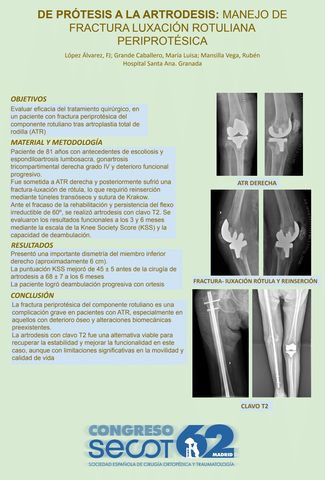

De Prótesis a la Artrodesis: Manejo de Fractura-Luxación Rotuliana Periprotésica

FRANCISCO JAVIER LÓPEZ ÁLVAREZ, MARIA LUISA GRANDE CABALLERO, RUBÉN MANSILLA VEGA